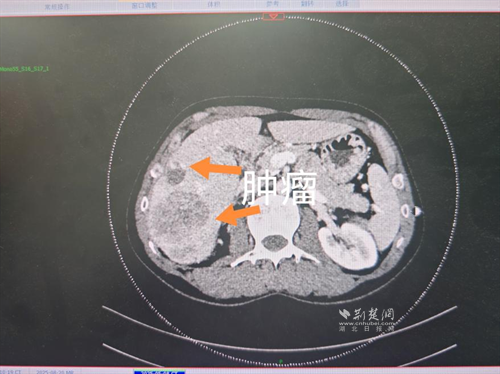

经过肝胆外科牵头组织的多学科MDT会诊,团队确认其适合接受当前国际先进的钇90树脂微球选择性内放射治疗。治疗仅一个月后,患者病灶即从10cm缩小至6cm;术后六个月复查显示,病灶体积进一步缩小近40%,影像学检查提示完全缓解,临床分期成功转化,达到手术切除标准。